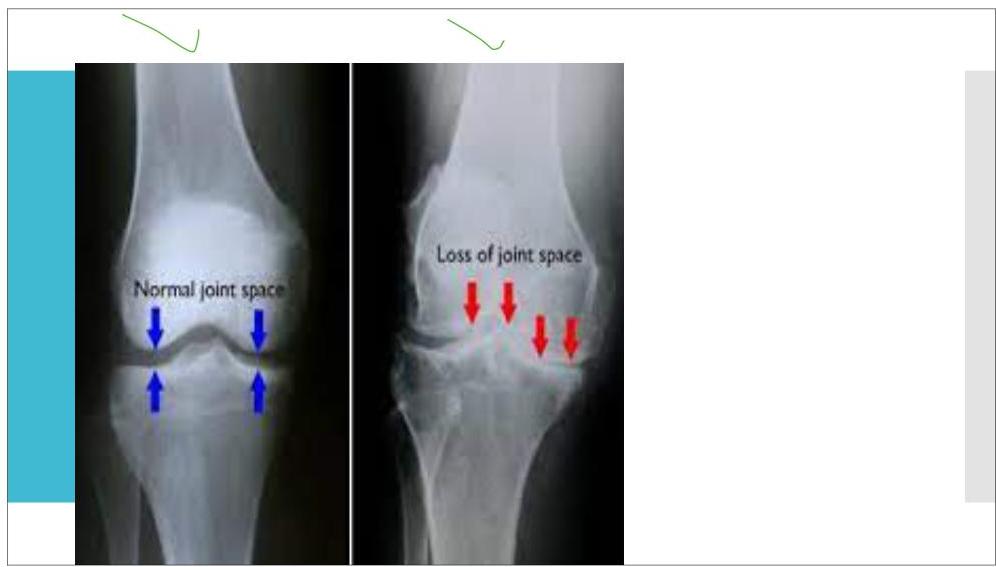

Surgical joint replacement